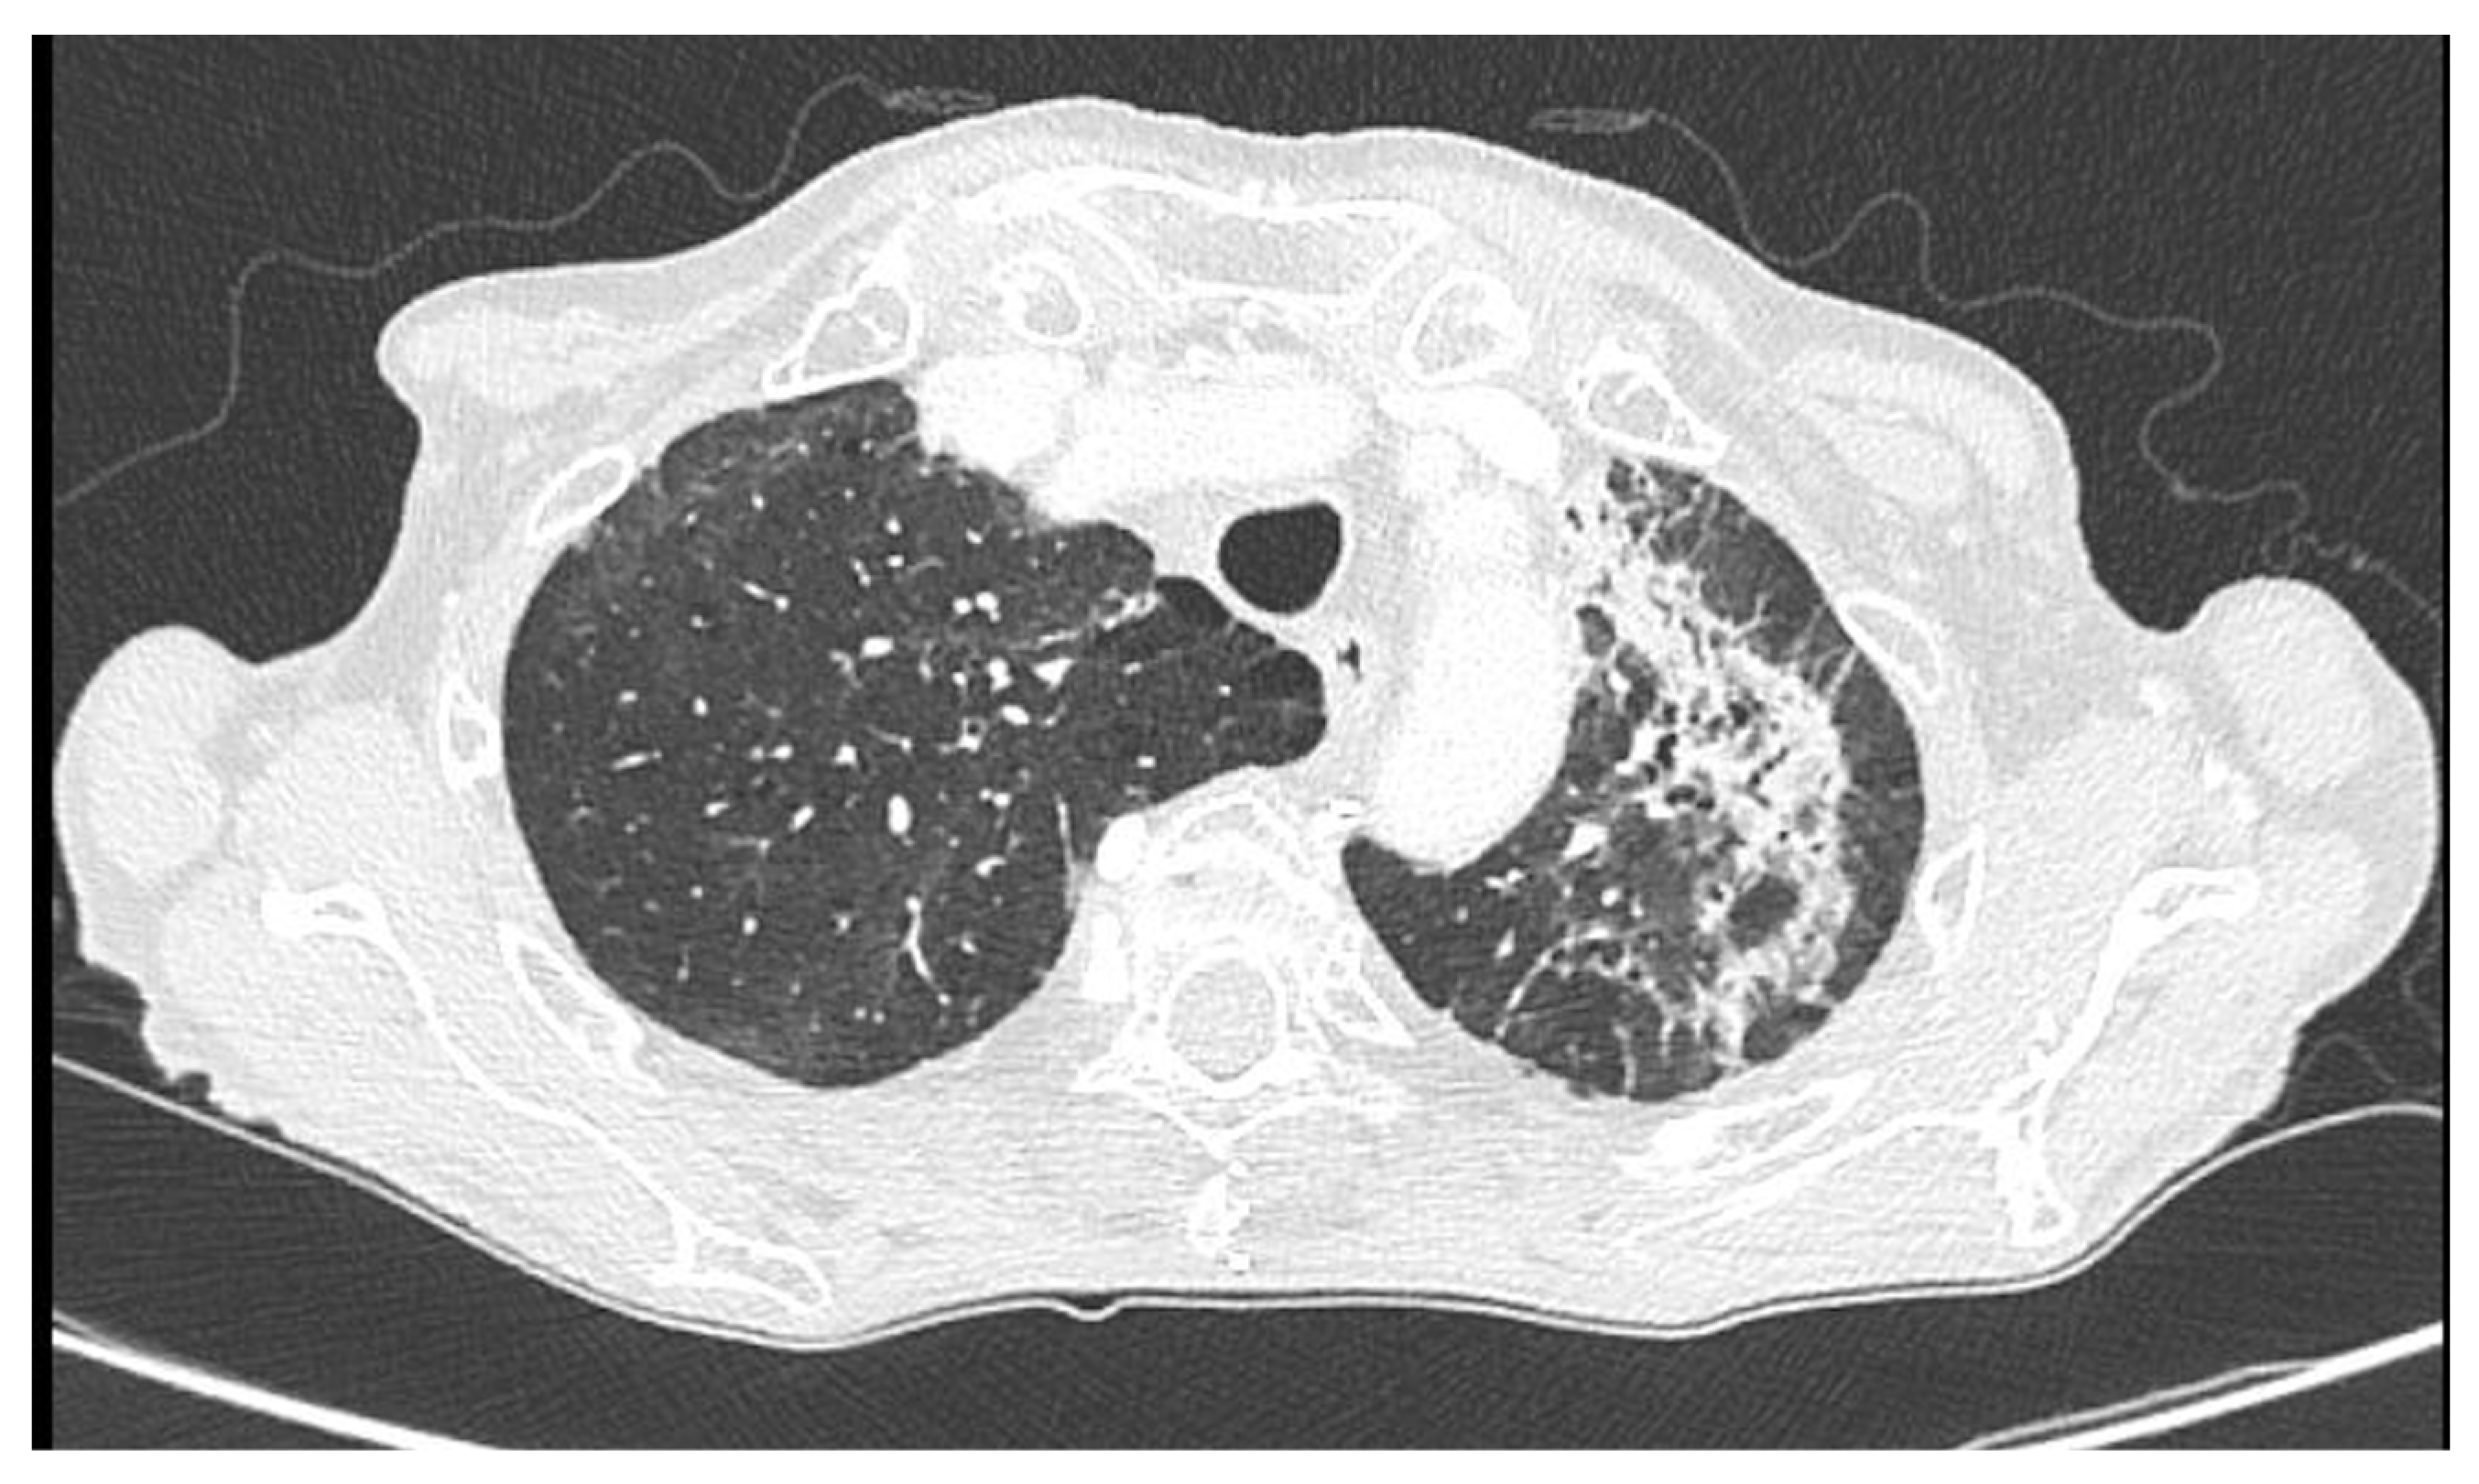

Mixed Infectious–Immune Pneumonitis Associated with PD-L1 Blockade: A Case of Durvalumab-Induced Lung Injury Complicated by Human Metapneumovirus Infection

2. Case Presentation